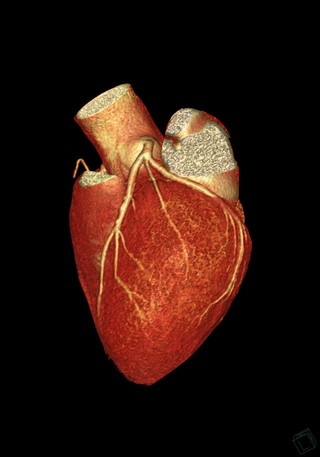

Artère coronaire droite 3D